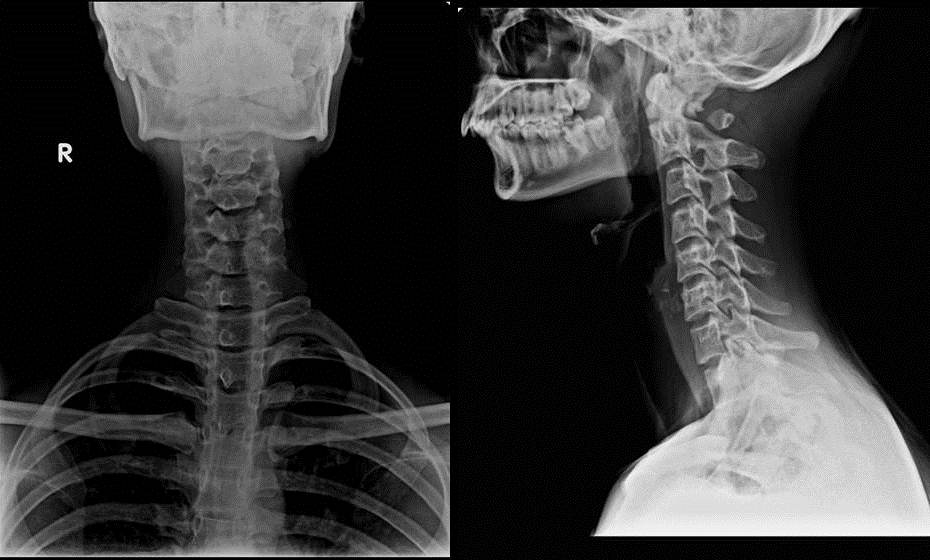

HYPOPLASTIC POSTERIOR ARCH OF ATLAS WITH FLOATING POSTERIOR TUBERCLE

AP and Lateral Radiographs of cervical spine showing absent posterior arch of atlas behind the lateral masses with free floating posterior tubercle. The lateral masses are well seen in AP radiograph.

D   Absence of posterior arch, with persistent posterior tubercle